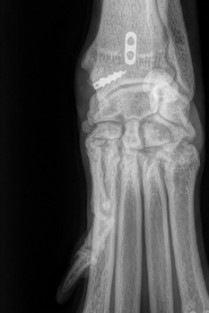

Le thème de cette 19ᵉ édition du Cours de Propédeutique, Sémiologie et Pathologie de l’Appareil Locomoteur à Bédoin sera d’explorer les extrémités. Nous poursuivons l’objectif qui fait la force de ce rendez-vous depuis ses débuts : offrir une approche à la fois rigoureuse, pratique et actuelle des affections locomotrices. À travers un programme structuré mêlant rappels fondamentaux, analyse sémiologique, stratégies diagnostiques et options thérapeutiques modernes, ce cours se veut résolument orienté vers la pratique clinique quotidienne. Les échanges, les discussions et les cas cliniques interactifs permettront d’enrichir l’expérience de chacun, quel que soit son niveau d’expertise. Nous espérons que ces journées seront l’occasion de consolider vos connaissances, d’actualiser vos pratiques et de partager des moments d’apprentissage stimulants dans un cadre propice aux échanges scientifiques et humains.

- Prendre en charge de manière approfondie des affections complexes des extrémités.

- Déterminer des stratégies chirurgicales adaptées grâce à l’analyse de cas cliniques interactifs.

- Intégrer les dernières avancées en matière de biomécanique, implants et orthèses.